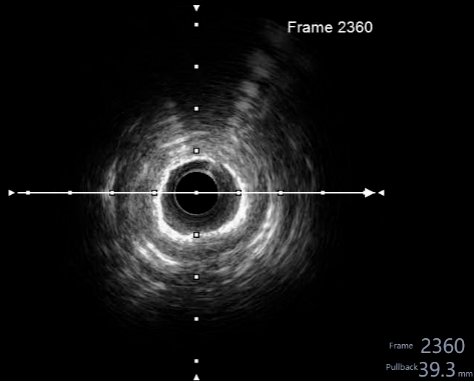

冠脉造影及介入治疗:将ACIST CVi血管造影注射系统调整至冠脉造影模式,完善冠脉造影。结果示:LM未见明显狭窄,LAD近端80%狭窄,严重钙化,IVUS可见360°钙化。回旋支少量斑块浸润,右冠状动脉30-40%狭窄。决定处理LAD,由于患者存在严重钙化,使用Shockwave球囊预处理打开钙化,后植入3.0*24mm +3.5*24mm药物涂层支架,效果满意。